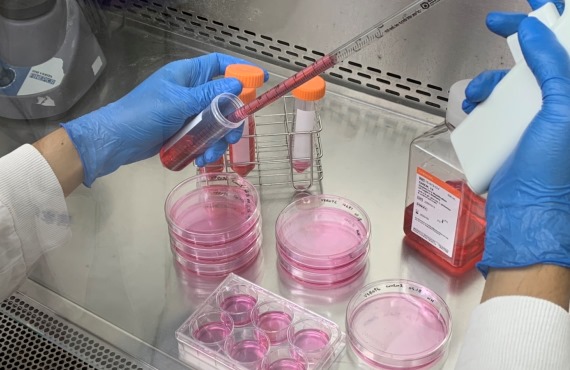

病毒培養與分離是病毒學研究中的重要技術與基礎,透過病毒培養獲得足夠的研究材料,能夠幫助研究人員瞭解病毒的生物學特性及病毒與宿主細胞之間的交互作用,並找出可能的預防與治療方法。然而,病毒培養存在著許多困難。由於病毒為絕對寄生的微生物,本身缺乏自主繁殖與生存的能力,必須依賴宿主細胞才能進行複製和增殖。研究人員需選用適合的細胞株、雞胚蛋或是動物,進行接種,並提供適當的營養與環境,確保細胞及病毒的生長和繁殖。最後從培養液或細胞中收取病毒,並進行鑒定和純化。整個過程皆需仰賴實驗室人員熟練的技術和豐富的經驗,也需要嚴格控制實驗室環境,避免交叉污染,影響材料品質以及防止病毒外洩,造成人員危害。 NIDB病毒資源庫有多種病毒培養的經驗,並提供各式重要人類病毒株分讓服務,以及病毒代培養服務,可滿足學術界及生技產業界研究所需。

仿真病毒泛指利用不同種類的病毒外殼蛋白與基因體製成的重組病毒,透過結合慢病毒包裹系統,可以生產出攜帶各式蛋白但卻無法再進行複製的重組慢病毒,使研究人員得以在常規生物安全等級第二級(BSL-2) 的實驗室操作。其應用範圍十分廣泛,包含研究病毒與宿主細胞受體的親和性、疫苗開發及抗體確效等。由於仿真病毒能有效降低研究風險,NIDB病毒資源庫也提供以慢病毒載體系統所製備之高效價仿真病毒作為研究媒介。